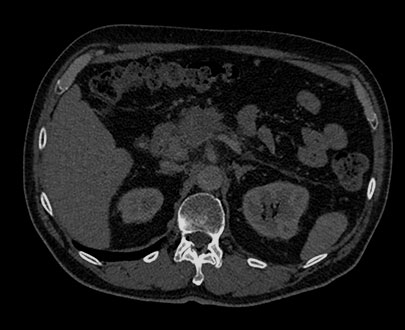

MonoE zakresie 40keV

Suwak wyboru energii 40kev

Badanie MonoE pozwala uzyskać zsyntetyzowane obrazy monoenergetyczne przy wstępnie zdefiniowanych wartościach w zakresie od 40 keV do 200 keV. Wygląd obrazów zmienia się wraz ze zmianą wartości keV, nawet jeśli ustawienia okna/poziomu są takie same. Przykładowo przy niższych wartościach keV jod może wydawać się jaśniejszy, natomiast wyższe wartości keV pozwalają ograniczyć artefakty pochodzące od metalowych implantów.